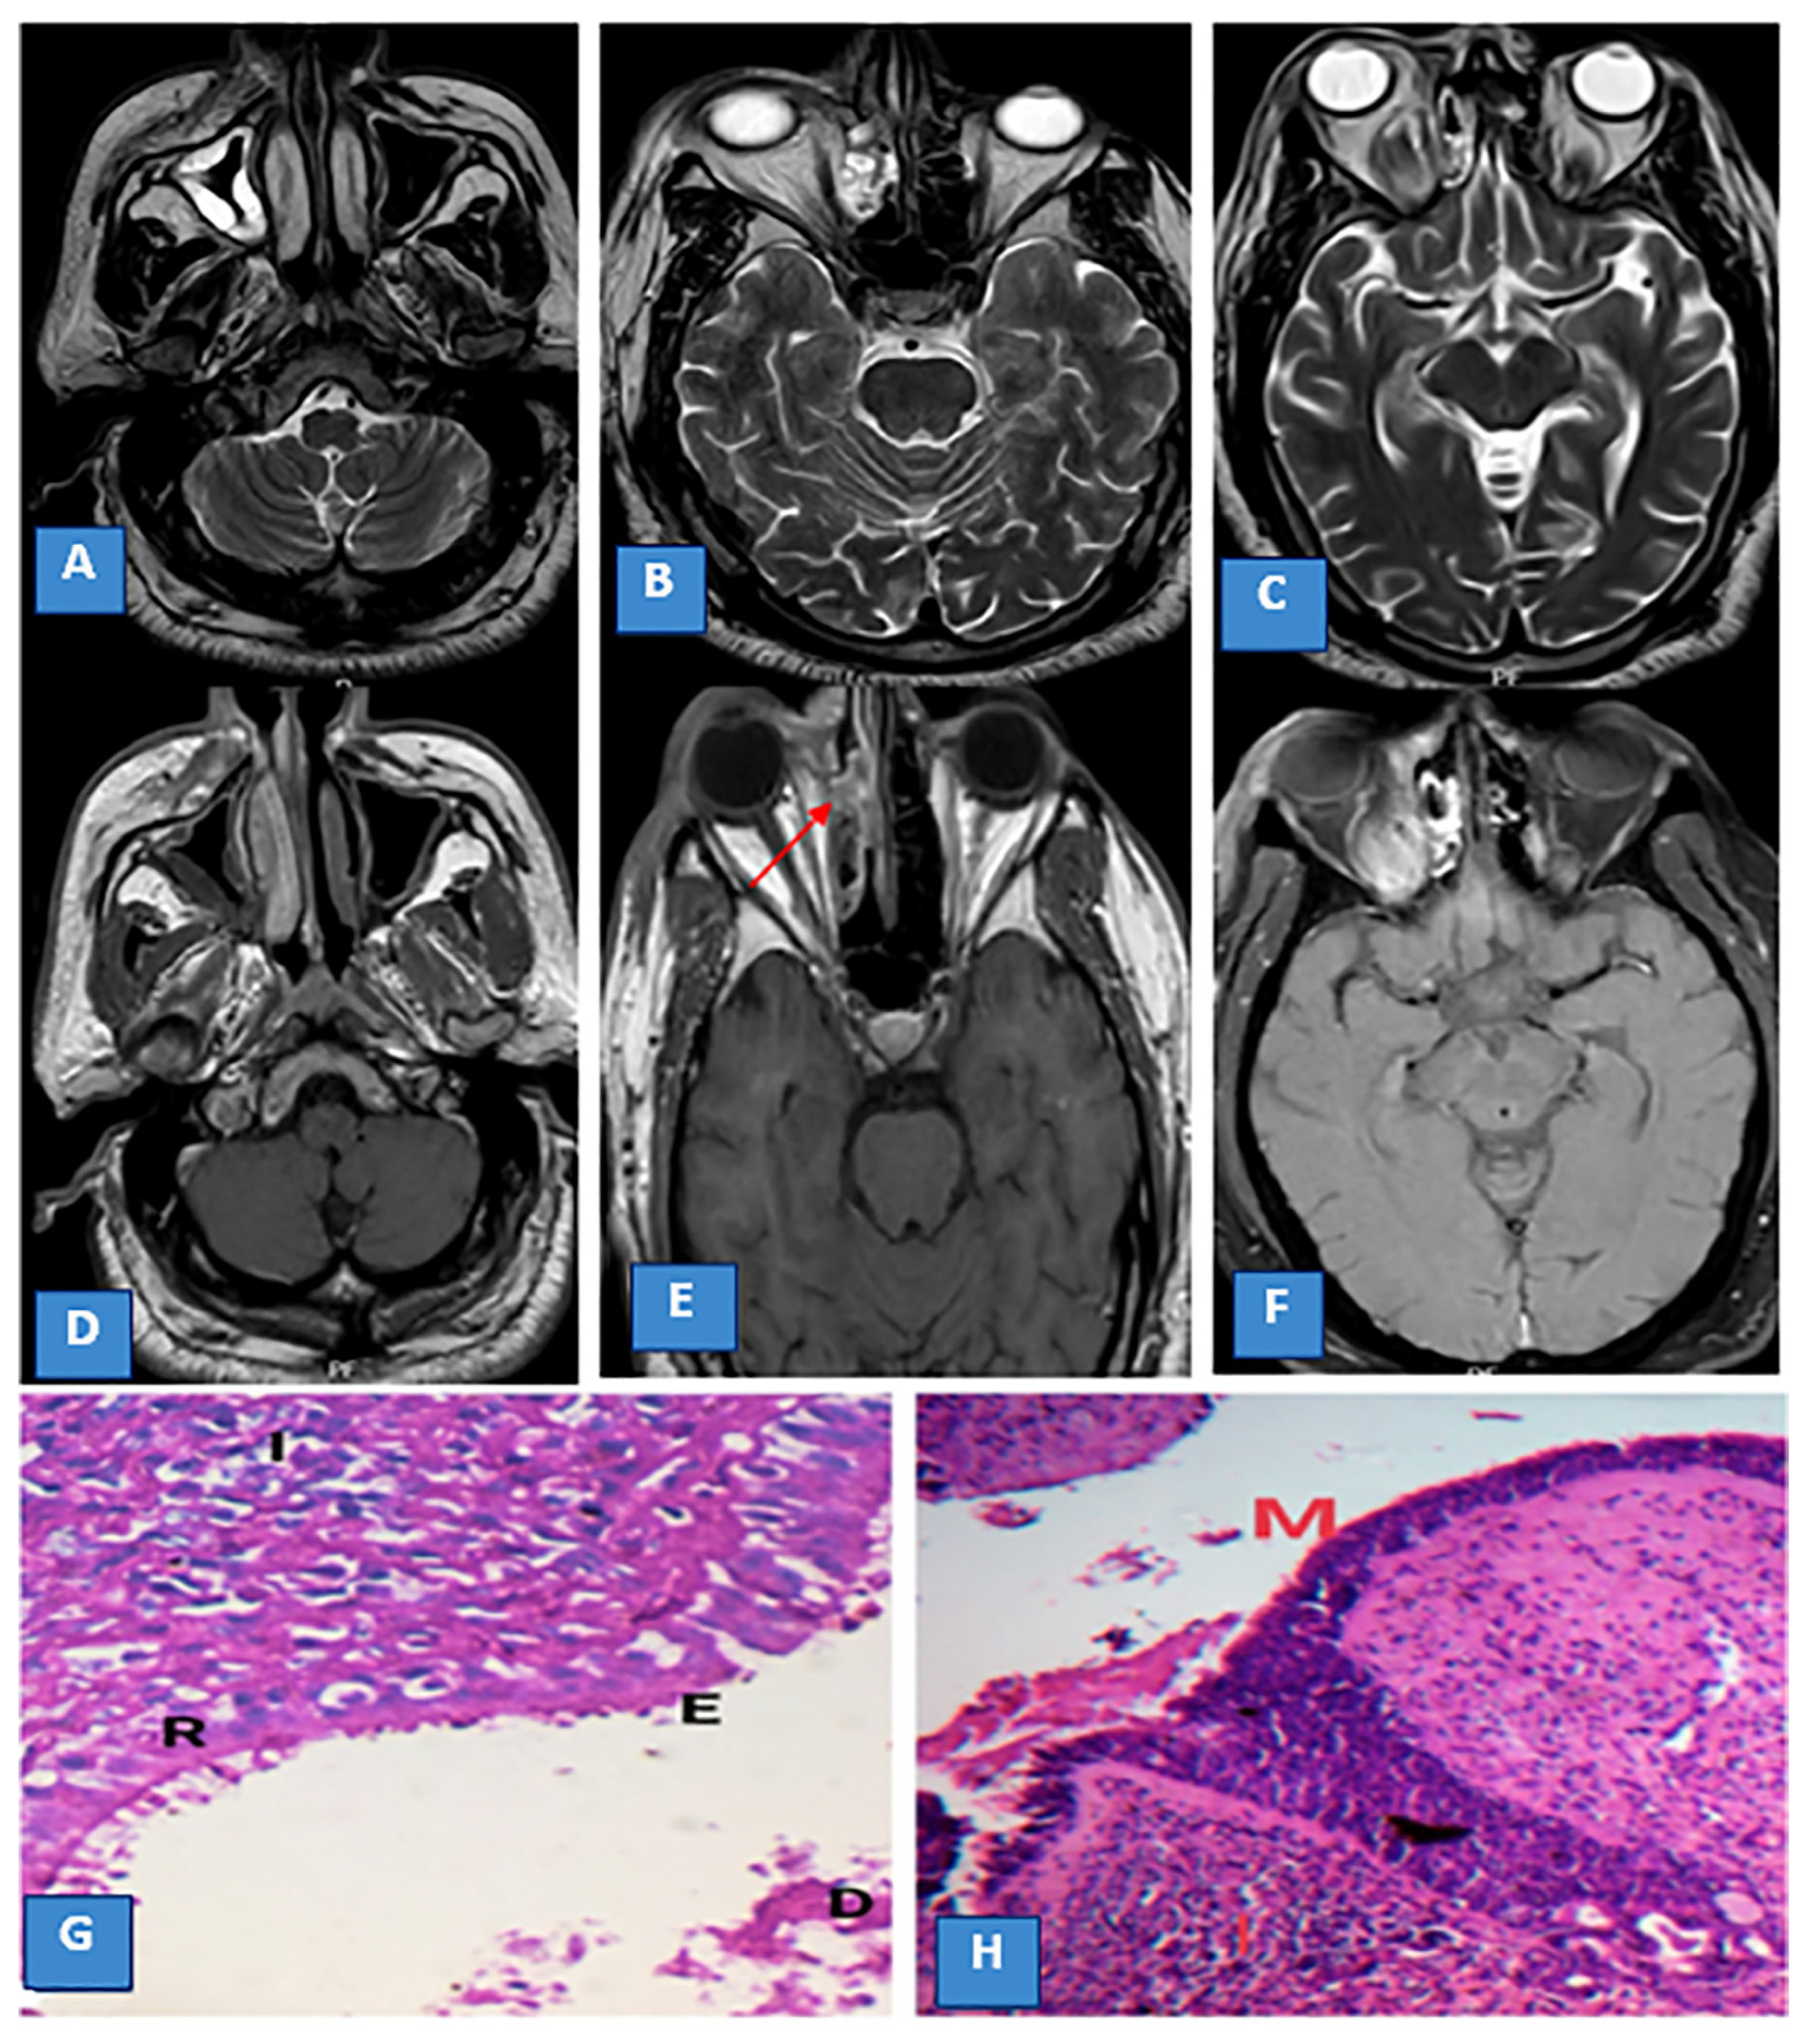

3.3. MRI Findings and Signal Characteristics

3.4. Extrasinus Extension

3.5. Histopathological Findings